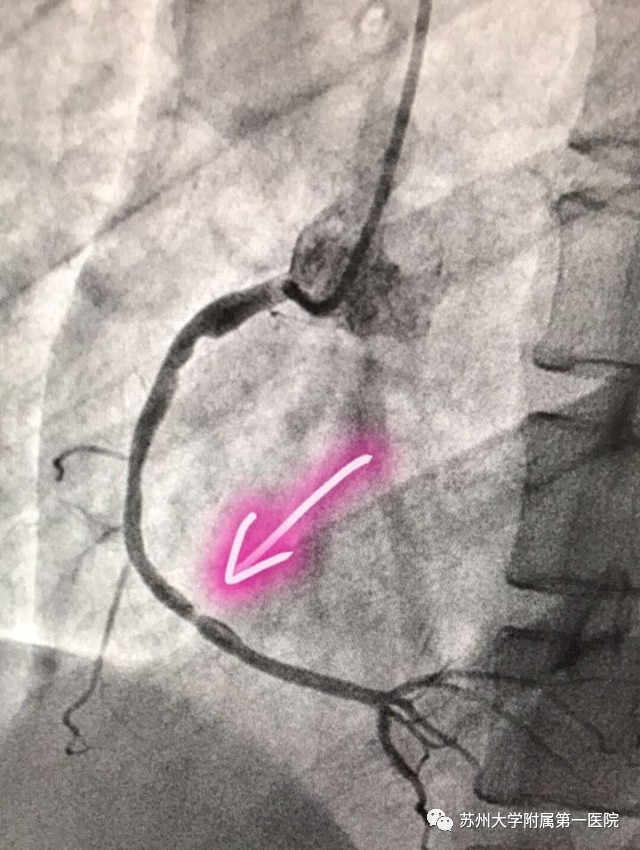

证实是右冠状动脉多处斑块形成,远端狭窄约80%!手术结束后手术医生对患者家属说:急诊的医生救了你的命,如果当时回家了那后果不堪设想!